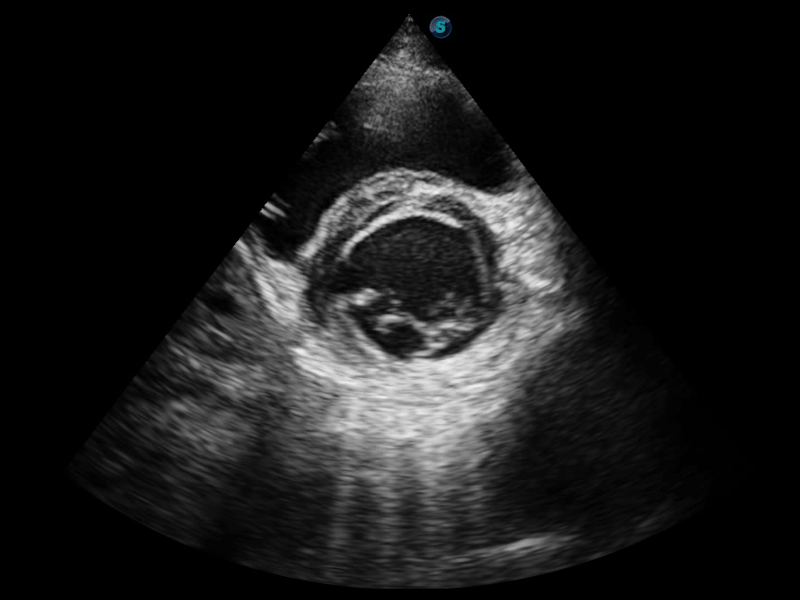

開立醫(yī)療通過不斷的技術(shù)創(chuàng)新,為大眾的生命健康提供持續(xù)關(guān)愛。P12 Plus采用全新一代超聲成像平臺,新平臺旨在將真實還原組織解剖結(jié)構(gòu)作為首要目標(biāo)。平臺采用全新集成化硬件模塊,搭載新一代芯片,系統(tǒng)性能得到大幅提升,為您的診斷提供了豐富的臨床信息。優(yōu)異的圖像表現(xiàn),豐富的探頭配置,全面的應(yīng)用功能,為您日常診斷提供了可靠的助手。

P12 Plus

彩色多普勒超聲診斷系統(tǒng)